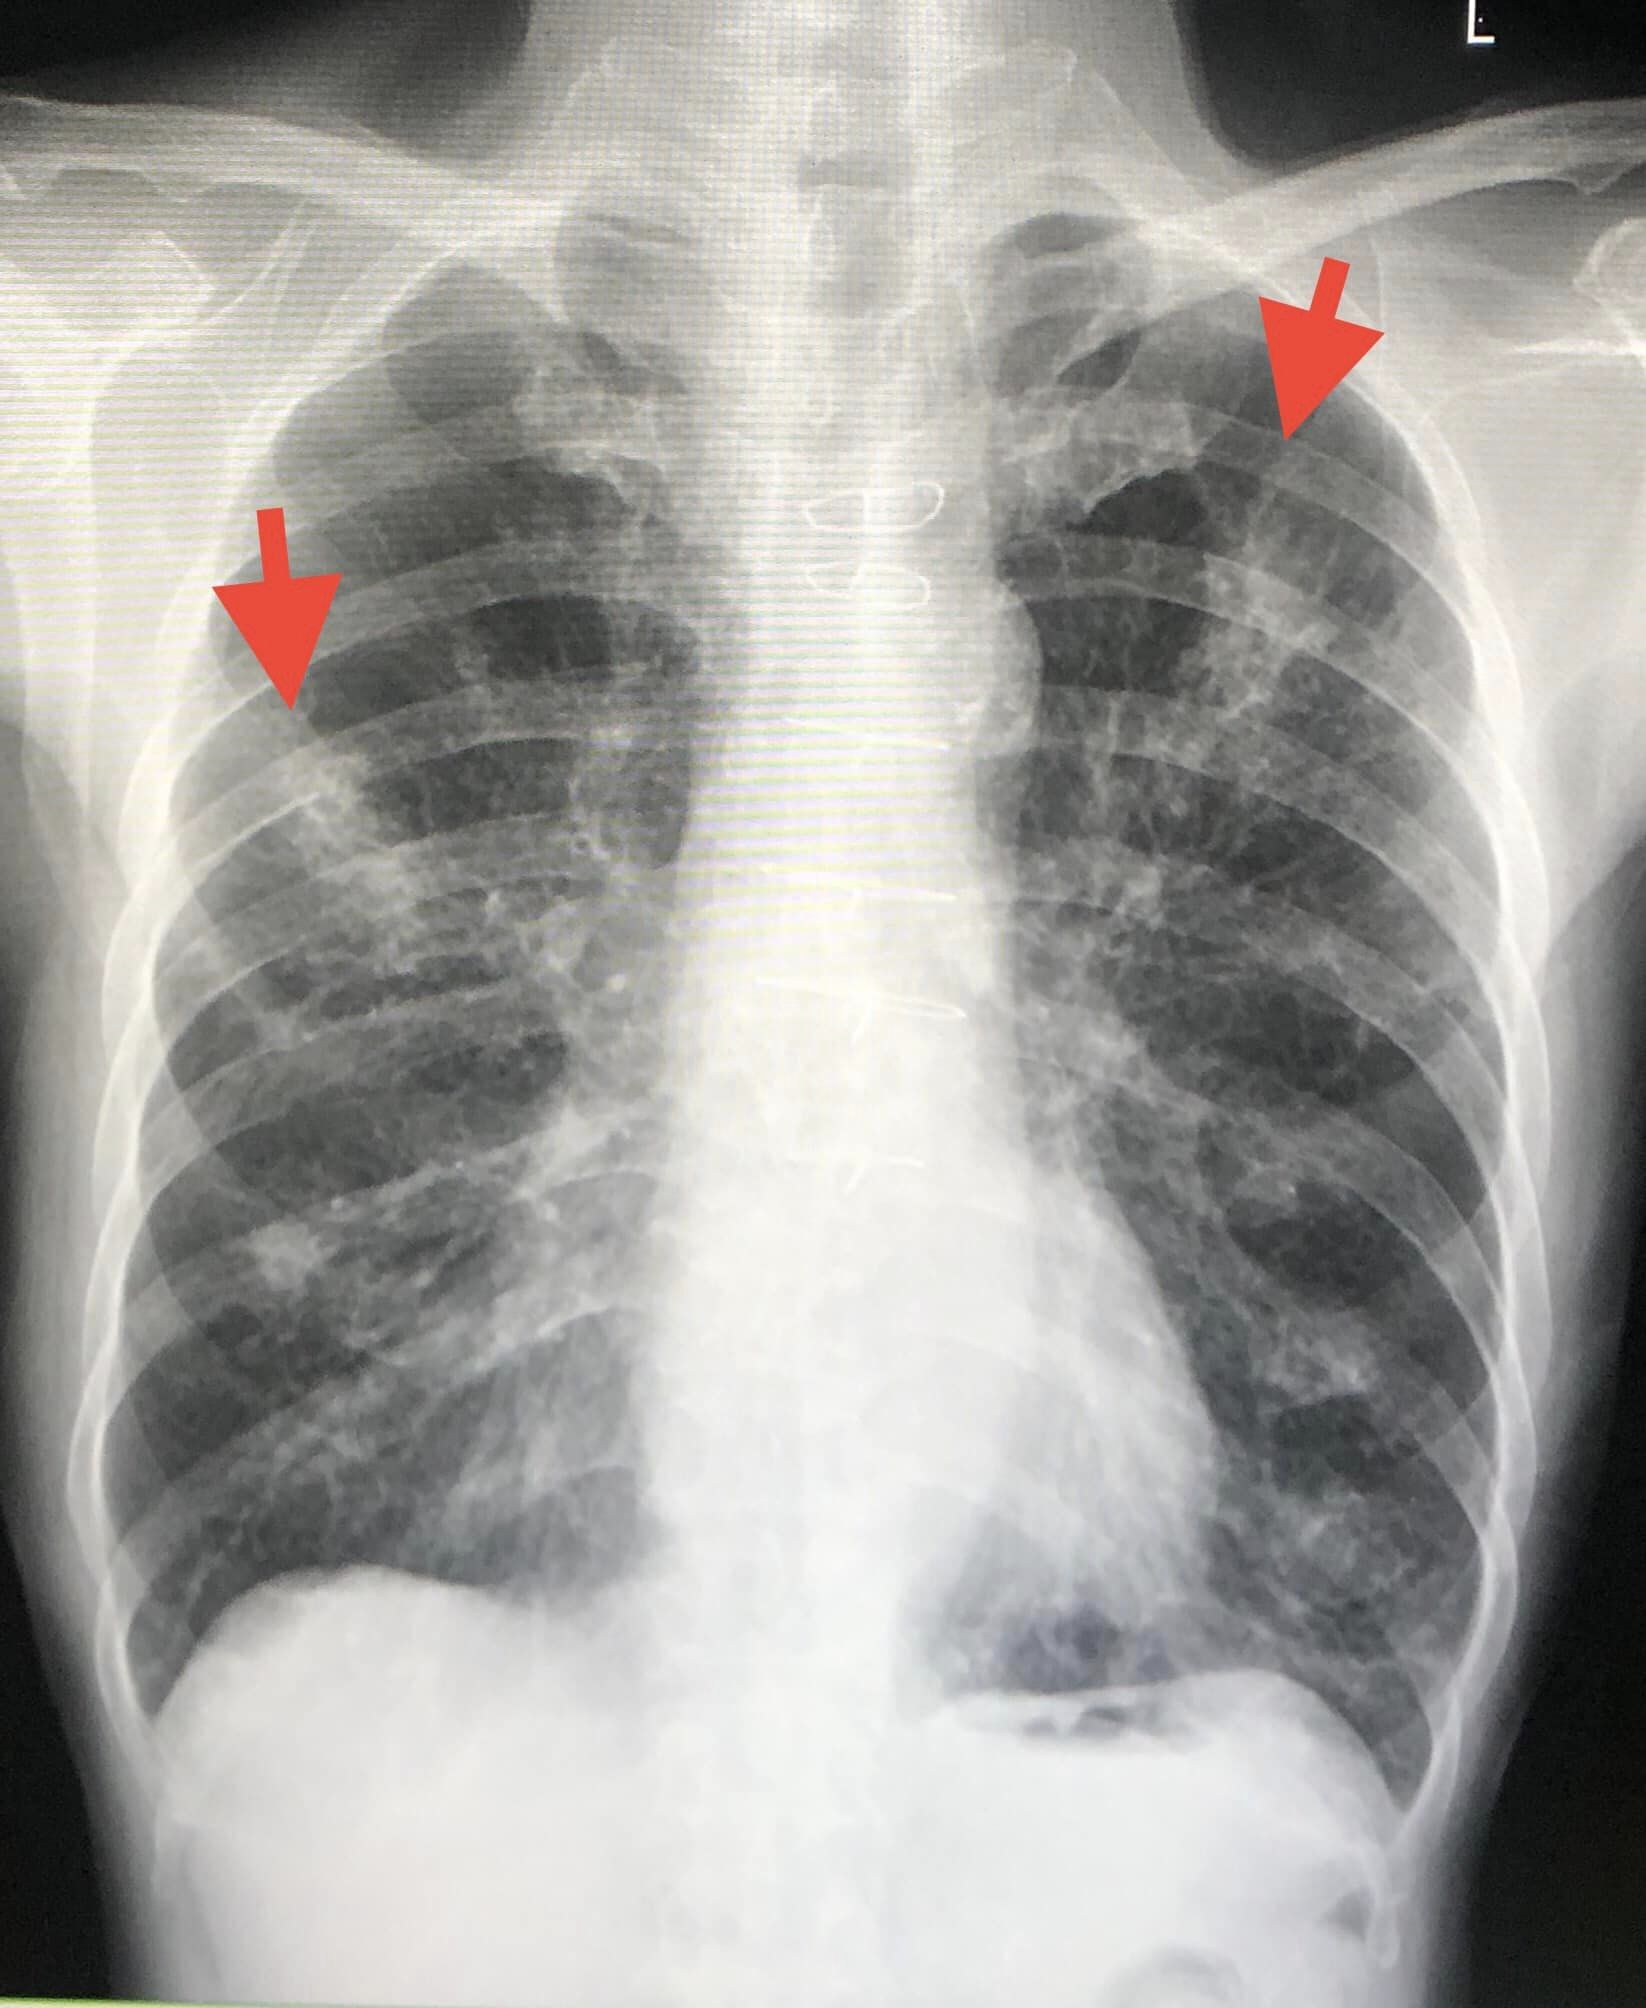

ผู้ป่วยชายอายุ 66 ปี ไอ เสมหะสีเหลืองเขียว มีไข้ต่ำๆ เหนื่อย หายใจวี๊ดๆ 10 วัน ประวัติเป็นโรคหลอดลมอุดกั้นเรื้อรัง เคยสูบบุหรี่ 2 ซอง/วัน หยุดสูบ 4 ปี เป็นโรคหัวใจขาดเลือด ทำผ่าตัดบายพาสหลอดเลือดหัวใจ 3 เส้น 4 ปีก่อน กินยาสเตียรอยด์ต่อเนื่อง 1 ปี เพราะเหนื่อยหายใจลำบาก ผู้ป่วยมีอาชีพรับซื้อขายข้าวโพดเลี้ยงสัตว์ และขายปุ๋ยเคมี (ดูรูป)

ตรวจร่างกาย ไม่มีไข้ อุณหภูมิ 37 องศาเซลเซียส ฟังปอดมีเสียงวี๊ด เอกซเรย์ปอด มีปื้นขาวเล็กๆในปอด 2 ข้าง (ดูรูป) คอมพิวเตอร์สแกนปอดมีฝ้าหลายจุดกระจายในปอด 2 ข้าง (ดูรูป) ทำหัตถการส่องกล้องเข้าไปในหลอดลม( Bronchoscopy) พบเสมหะเหลืองข้นเหนียวมากในหลอดลมทั้ง 2 ข้าง ดูดออกมาได้เยอะมาก ส่งน้ำล้างปอด ย้อมไม่พบเชื้อวัณโรค ย้อมพบเชื้อราสาย เพาะเชื้อราขึ้นเชื้อรา Aspergillus fumigatus และ Rhizopus spp. (ดูรูป) ส่งน้ำล้างปอด bronchial Aspergillus galactomannan antigen ให้ผลบวก